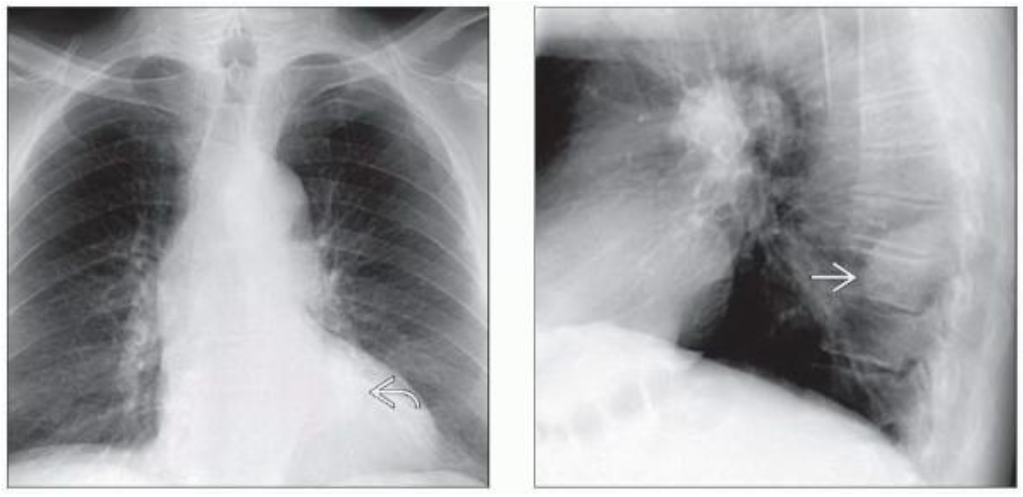

(左)82岁男性,无症状,椎旁神经鞘瘤。PA胸片显示左侧心后纵隔轮廓轻微异常。

(右)同一患者的侧位胸片显示肿块位于椎旁,由于位于肺外,可见不完整的肿瘤边界。该发现高度提示PNST,进一步MR评估可排除椎管内生长。